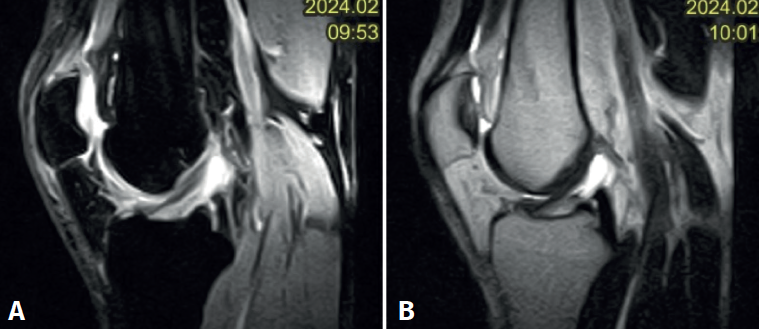

En ambos pacientes se realizó anestesia raquídea para realizar la cirugía y se utilizó manguito de isquemia a nivel del muslo. Se colocó al paciente en decúbito supino, utilizando un soporte en U en el tercio distal del muslo para la fijación de la extremidad. Se realizaron los portales artroscópicos habituales anterolateral y anteromedial, objetivando en la exploración diagnóstica de la rodilla la presencia de un ganglión localizado en el fascículo posterolateral del LCA (Figura 3) que, cuando se realizaban los movimientos de flexión y en posición de cuatro, se pinzaba en el espacio articular tibiofemoral externo. Para realizar la resección artroscópica del quiste se colocó al paciente en la posición “de cuatro”, facilitando la diferenciación anatómica de los fascículos anteromedial y posterolateral del LCA, tal y como proponen Hopper G et al.(4). Se realizó la disección y exéresis cuidadosa del quiste con una pinza basket, un terminal shaver de 4 mm y un terminal de ablación por radiofrecuencia (Figura 4). Al finalizar la resección del quiste, se realizó una nueva exploración dinámica de la rodilla, donde se evidenció la ausencia de pinzamiento entre el LCA, el cóndilo femoral y el platillo tibial lateral, a la vez que se comprobó la estabilidad del remanente del LCA (Figura 5).

Figura 4. Visión artroscópica desde el portal anterolateral. Se introduce a través del portal anteromedial el instrumental. A: inicio del desbridamiento del quiste con un basket artroscópico; B: se continúa el desbridamiento del quiste con un shaver de 4 mm respetando las fibras del ligamento cruzado anterior sano.

En el postoperatorio se autorizó la movilidad y la carga progresiva con bastones según la tolerancia. En ambos pacientes la sintomatología dolorosa y las restricciones de movilidad articular se resolvieron completamente. No se realizó RM de control en ninguno de los dos casos.

Figura 5. Visión artroscópica desde el portal anterolateral. A: tras el desbridamiento se observa que no existe pinzamiento del espacio articular femorotibial lateral en posición “de cuatro” a 90° de flexión; B: palpación de la tensión del remanente del ligamento cruzado anterior.